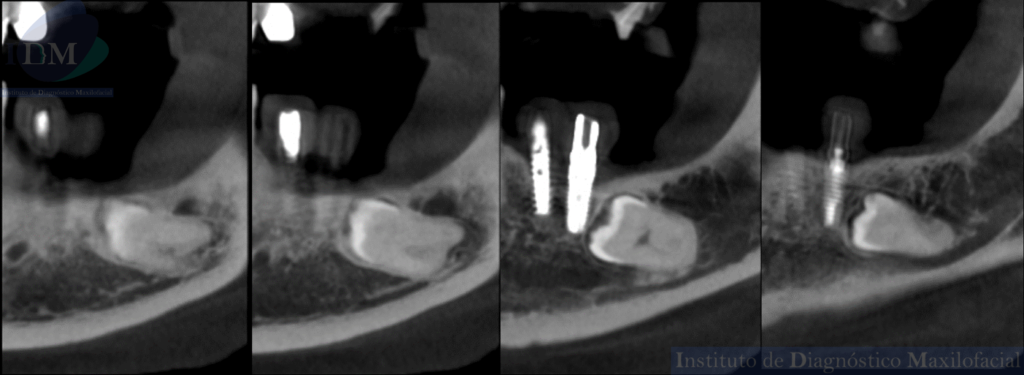

CORTES TANGENCIALES

A la evaluación de la radiografía panorámica se evidencia reabsorción ósea alveolar bimaxilar, edéntulo parcial bimaxilar y presencia de múltiples implantes con prótesis sobre implantes así como tratamientos restaurativos. Siendo lo más destacado una molar retenida en cuerpo mandibular izquierdo, la cual esta mesioangulada.

Siendo así que en la tomografía volumétrica de haz cónico se evidencia una hipercementosis radicular, con los segmentos radiculares contactando con el conducto dentario inferior. Finalmente se evidencia un borramiento del espacio del ligamento periodontal compatible con anquilosis dentaria.